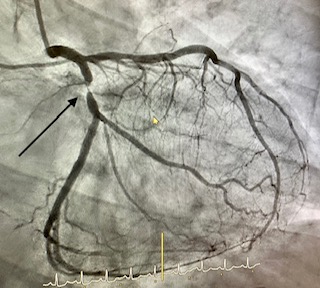

Angioplàstia amb stent

L'angioplàstia coronària transluminal percutània amb implantació de stent ha estat capaç, a les sales de RX dels laboratoris d'Hemodinàmica i Cardiologia Intervencionista, de combatre eficaçment a la malaltia que més mortalitat causa en les societats modernes: la malaltia coronària.